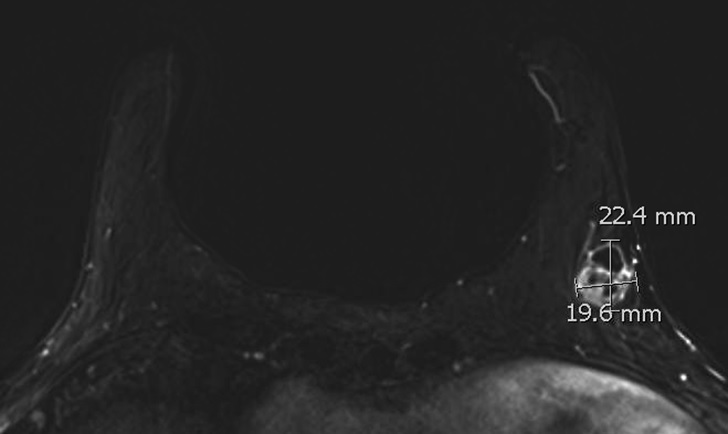

الحالة الأخيرة: كتلة صغيرة جدا في الثدي الأيسر. تم عمل رنين مغناطيسي واكتشاف انتشار للغدد اللمفاوية المجاورة. تم علاج المريضة واستئصال الكتلة والغدد بشكل كامل.